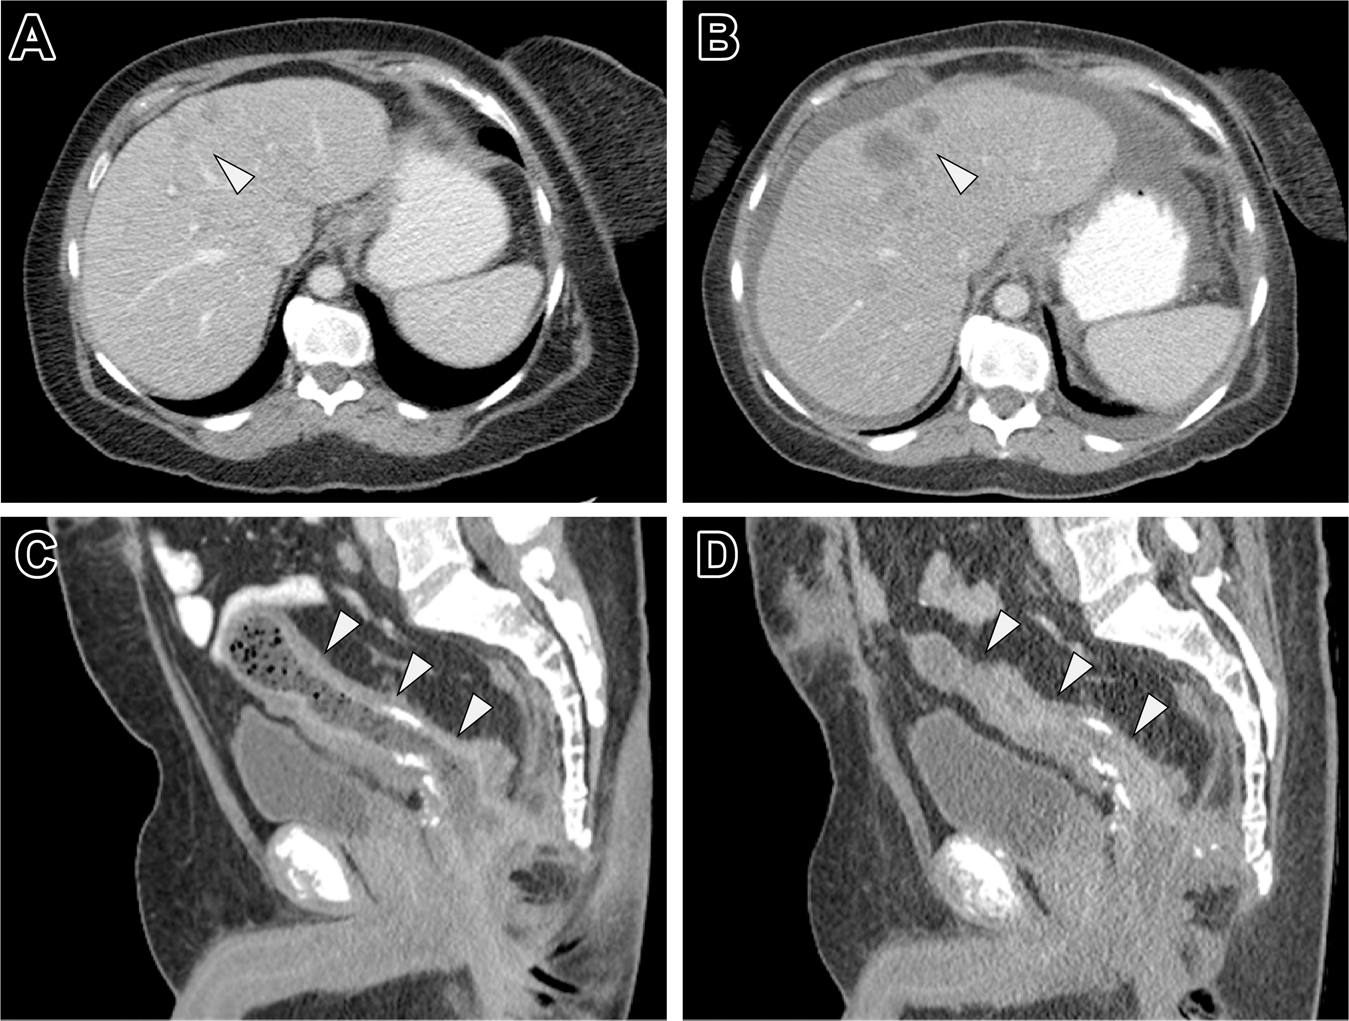

Fig. 2: An EGFR inhibitor-based treatment regimen was characterized by disease progression in patients with KRAS-amplified mCRC.

Case 9 (Table 2) was a 60-year-old female with mCRC to the liver (white arrowhead) that failed first line FOLFOX and bevacizumab (a) and continued to progress after 3 months on FOLFIRI and panitumumab (b). Similarly, Case 1 (Table 2) was a 49-year-old male with ulcerative colitis, status post subtotal proctocolectomy, and developed an adenocarcinoma of his rectal cuff (c, white arrowhead). Surgical resection was aborted upon identification of peritoneal carcinomatosis and, thus, the patient received six cycles of FOLFOX and panitumumab. However, the patient’s disease continued to progress within 4 months and resulted in excessive distal colonic stricturing (d).